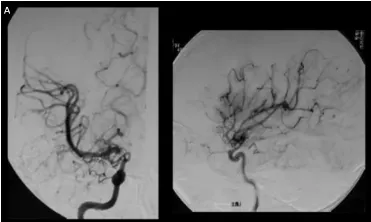

A,春奈术前右颈血管造影显示,在颈内动脉末端顶部,血管烟雾弥漫性发育,大脑中动脉扩张。

相比之下,小春因早期发现和诊断,成功避免了严重的神经功能损伤。川岛教授为她实施颞浅动脉-大脑中动脉STA-MCA双吻合术后,未出现任何神经功能损伤,术后影像显示血供重建良好。